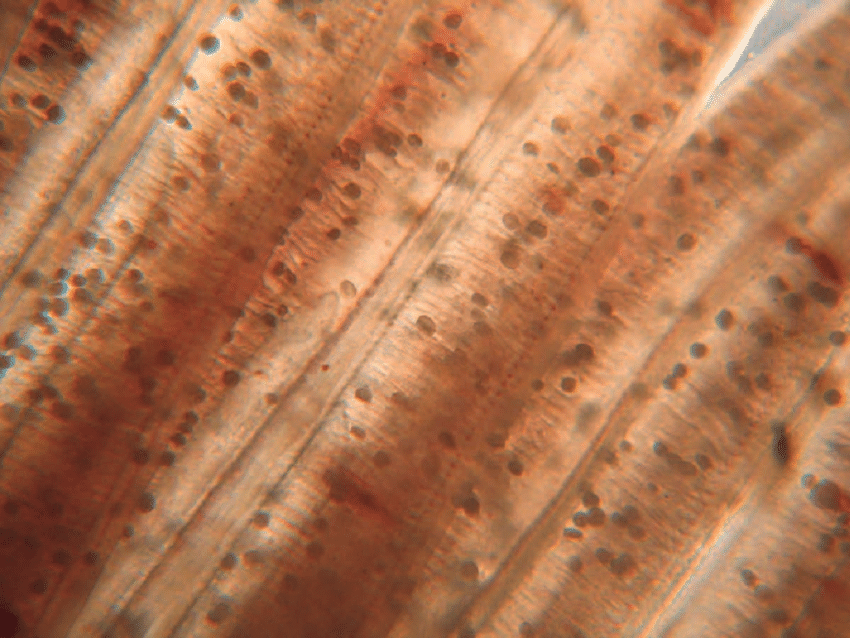

amyloodinium

مخملک